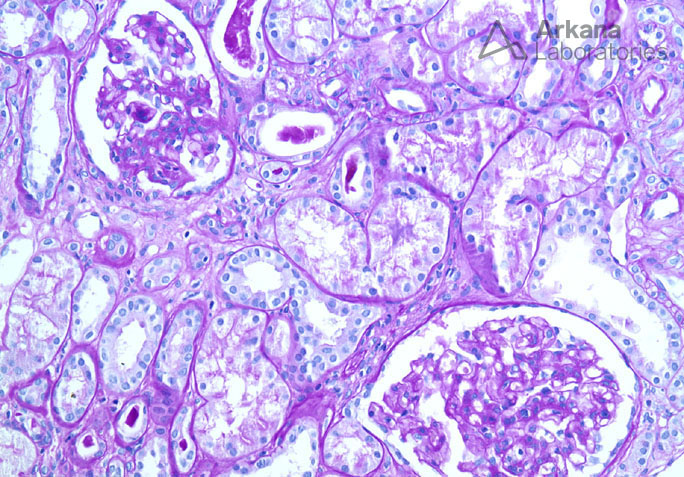

Previous Image Next Image Mesangial Expansion and Loop Adhesion in IgA Nephropathy on PAS Like Loading...